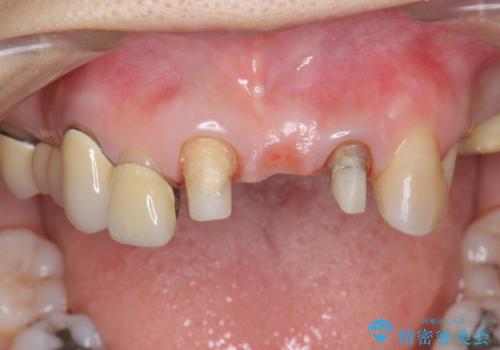

前歯ブリッジのやりかえ

- 前歯の審美障害、見た目の改善を希望され来院されました。

歯肉縁下カリエスも認められるため、挺出を行いセラミックブリッジを審美的に新製します。

- 47万円(仮歯×3・ファイバーコア×2・ジルコニアクラウン×3 歯の挺出)費用は治療当時の料金となります

虫歯が深くなった場合、挺出や歯周外科を行い歯周組織の状態を改善することでより安定した状態で予知性の高いセラミックブリッジを製作することが可能となります。